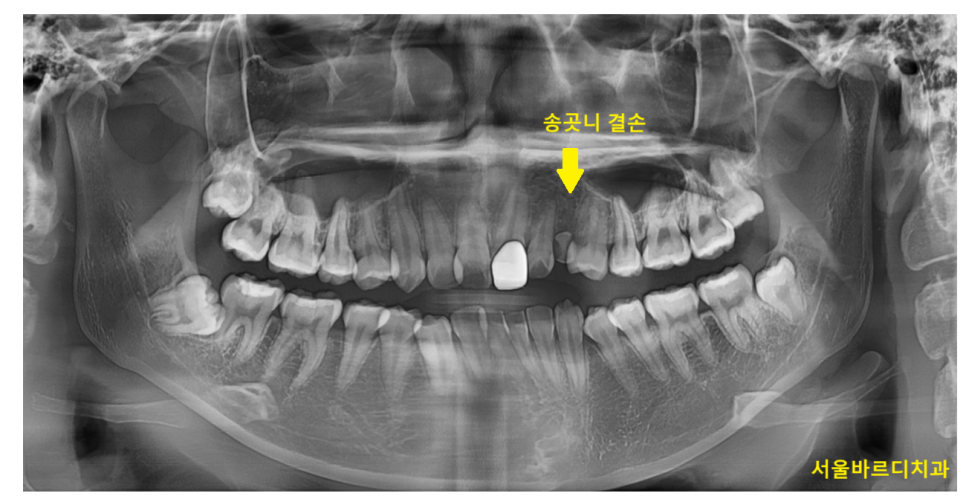

치아 개수의 결손

타고나기를 치아 개수가 양쪽에 차이가 있을 수 있습니다.

임플란트를 하기에 공간이 애매하다거나 할 경우

중심선이 안맞을 수 있어요~